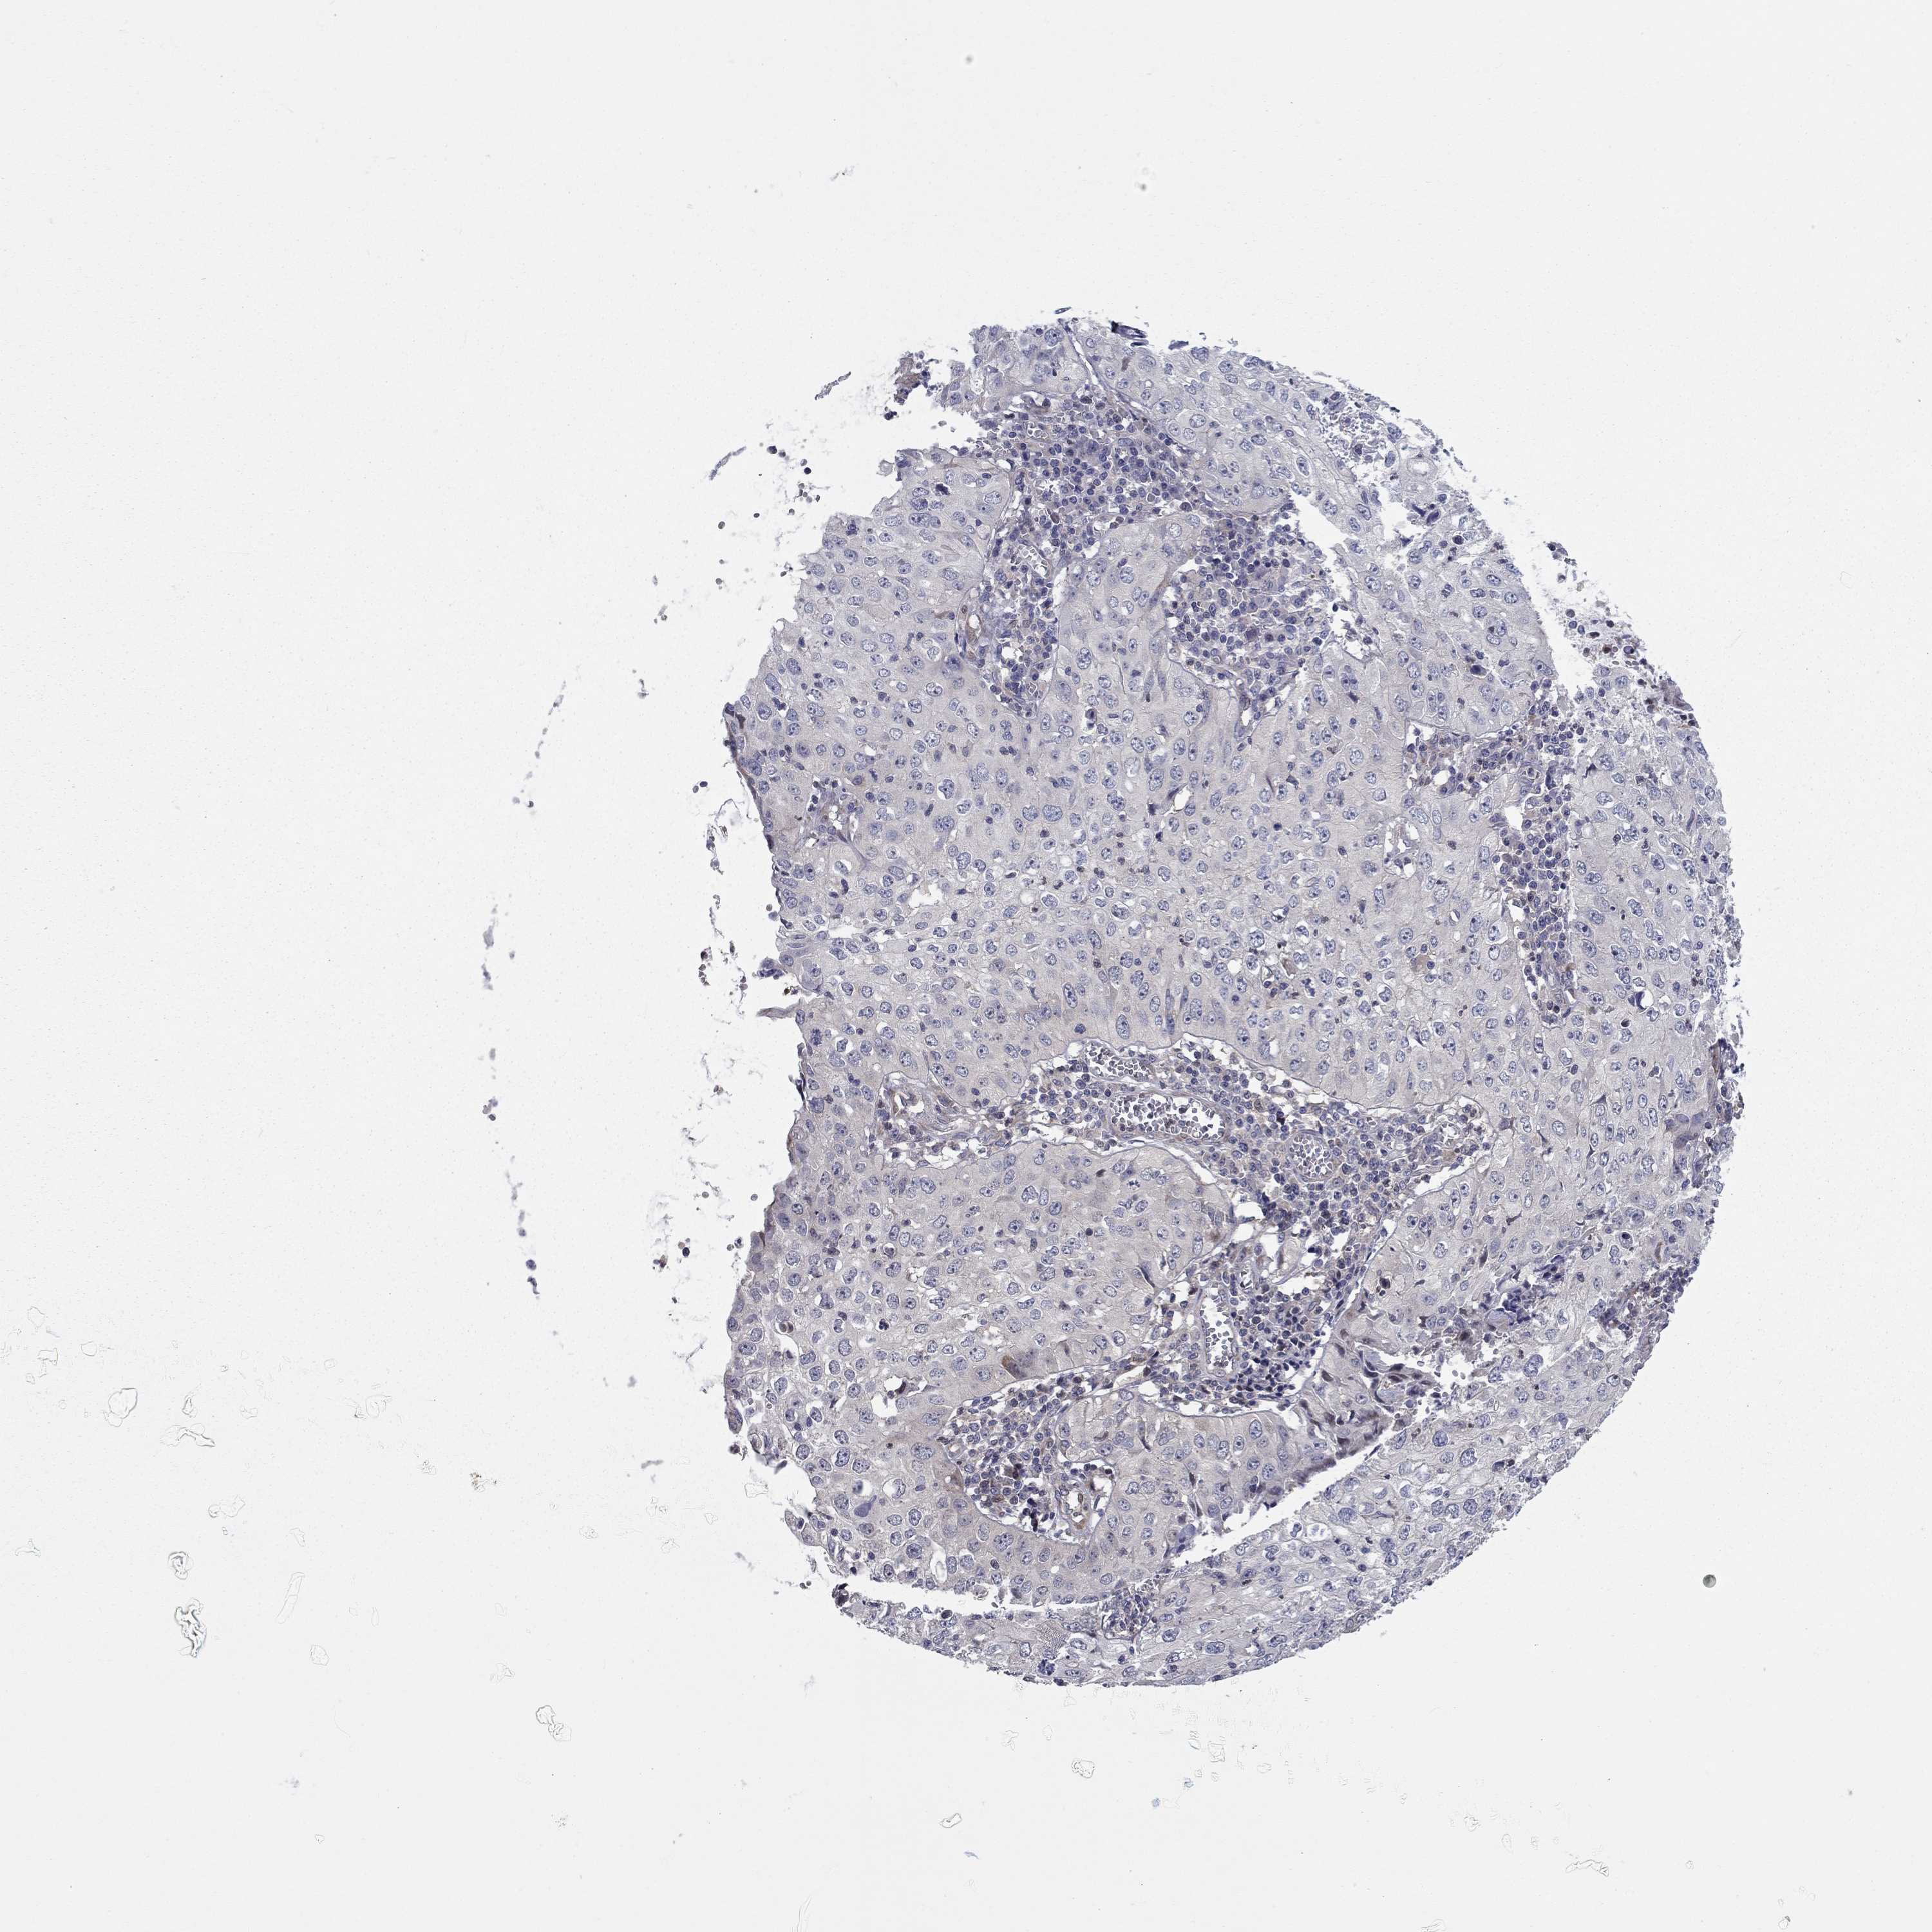

CERVICAL CANCER - Protein expressioni

A mouse-over function shows sample information and annotation data. Click on an image to view it in a full screen mode. Samples can be filtered based on level of antibody staining by selecting one or several of the following categories: high, medium, low and not detected. The assay and annotation is described here.

Note that samples used for immunohistochemistry by the Human Protein Atlas do not correspond to samples in the TCGA dataset.

Antibody stainingi

Antibody staining in the annotated cell types in the current human tissue is reported as not detected, low, medium, or high, based on conventional immunohistochemistry profiling in selected tissues. This score is based on the combination of the staining intensity and fraction of stained cells.

Each image is clickable and will lead to virtual microscopy that enables deeper exploration of all samples and also displays staining intensity scores, fraction scores and subcellular localization as well as patient and tissue information for each sample.

Antibody HPA073007

Staining

High

Medium

Low

Not detected

Intensity

Strong

Moderate

Weak

Negative

Quantity

>75%

75%-25%

<25%

None

Location

Nuclear

Cytoplasmic/membranous

Cytoplasmic/membranous,nuclear

Squamous cell carcinoma, NOS

Adenocarcinoma, NOS